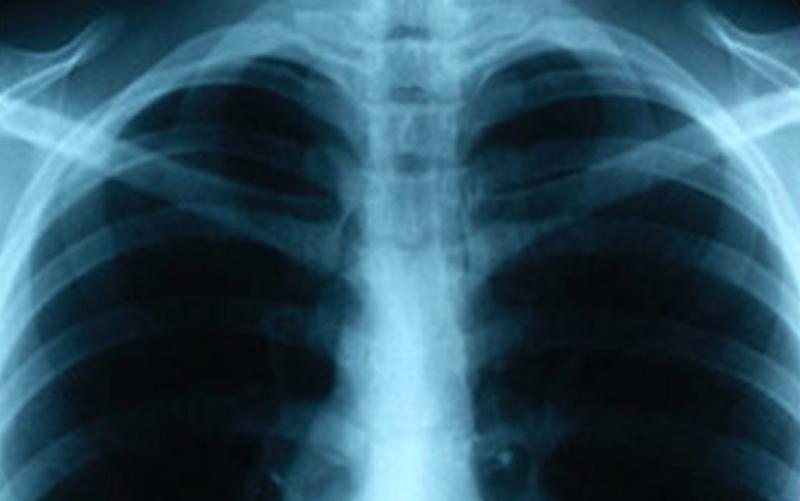

An individual who attends Southwestern College was recently diagnosed with tuberculosis (TB) and may have exposed students and staff to the disease, the San Diego County Health and Human Services Agency (HHSA) reported today.